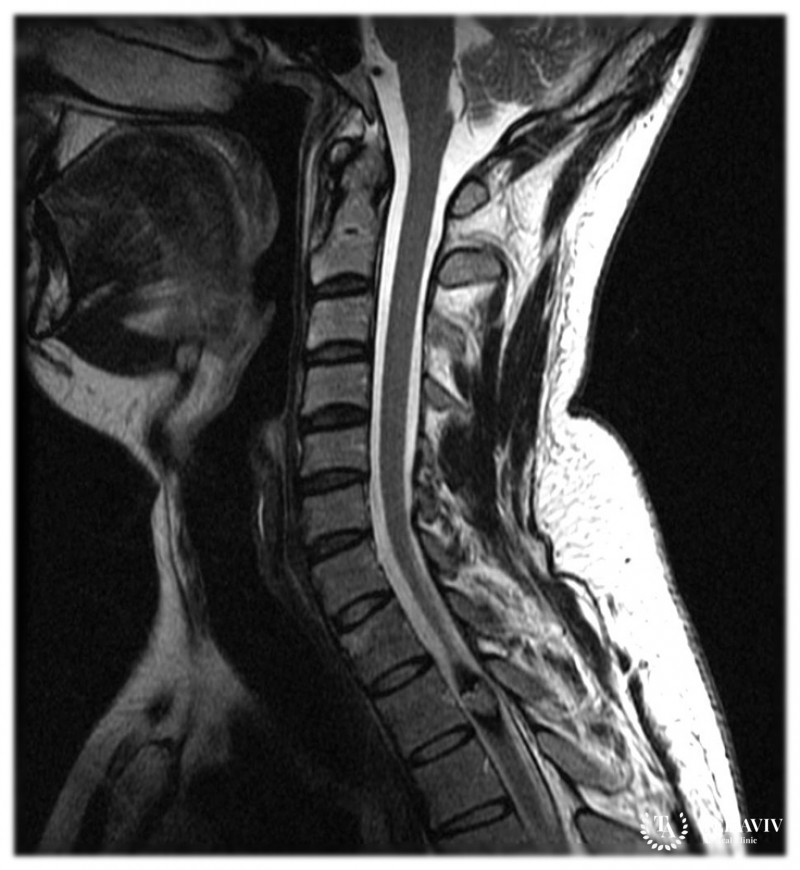

- Магнитную, резонансную томографию. Наиболее информативная методика показывает каверному, независимо от ее размера. Аппарат позволяет сделать поверхностный, глубокий снимок спинного мозга. Рекомендуется использование контрастного вещества;